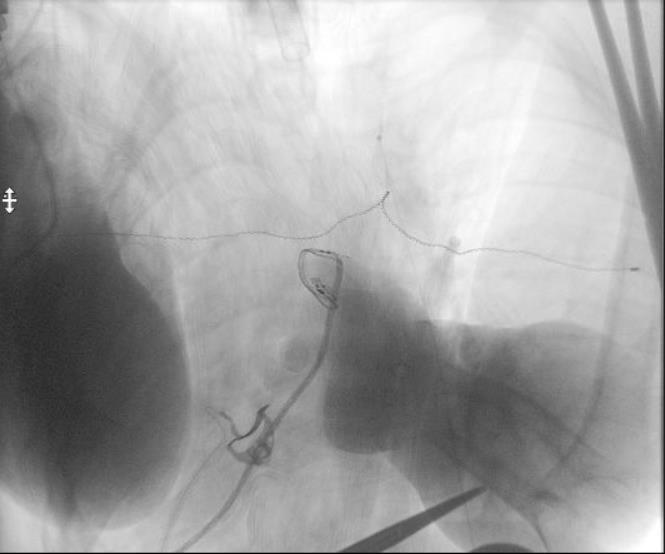

SDR involves surgically accessing the spinal cord (typically in the lumbosacral region, L2 to S1 or S2).The dorsal (sensory) nerve roots are carefully identified and then divided into smaller bundles called rootlets.

Adductor Longus L2, L3

Vastus Lateralis L3,L4

Tibialis Anterior L4, L5

Peroneus longus L5, S1

Gastrocnemius S1, S2

Abductor hallucis S1, S2

Sphincter S2

0 Unsustained or single discharge to train of stimuli

1+ Sustained discharge of appropriate muscle group. Ipsilateral response

2+ Sustained discharges of adjacent muscle groups, Ipsilateral

3+ Sustained discharges of distant muscle groups, Ipsilateral

4+ Sustained discharges of contralateral muscle group(s), with or without ipsilateral muscle group involvment